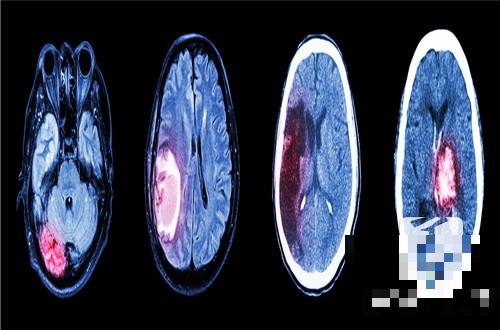

脑出血半边瘫痪是非常严重的,需要家人的护理,并且要进行规律的康复训练,这是脑部的神经受损导致的,能否恢复需要看脑出血量和出血的位置,情绪的波动异常,季节和气温的变化,不良的生活习惯都会出现脑出血,脑出血半瘫痪后需要卧床休息,使用镇静类的药物来进行治疗,严重的需要做手术治疗,患者家属都是希望病人可以恢复健康的,那么脑出血半边瘫恢复的几率高吗?

脑出血患者在出血发生之后,常会造成一定程度的肢体的瘫痪,对于肢体没有完全偏瘫的患者,只是肌力减退的患者,他的恢复希望还是比较大的,如果在出血发生之后,患者出现了一侧肢体的完全偏瘫,肌肉都没有收缩的情况下,那么这种情况,完全恢复是有一定困难的,但是经过积极的手术治疗,药物治疗以及后续的康复治疗,患者的肌力,都能有一定程度的改善,虽然不能完全恢复到,出血之前的状态,但是能恢复患者的生活完全自理,也是一件不错的事情。